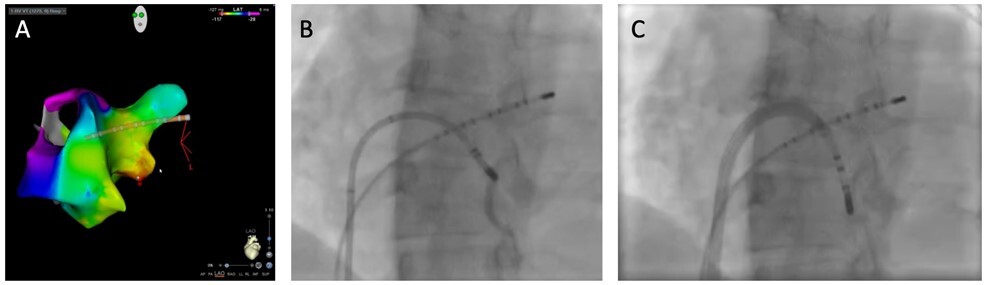

A) Aktivierungsmap der VT (LAO) mit frühester Aktivierung in der MCV (roter Bereich). B) Angiographie der MCV über den Ablationskatheter. C) Position des Cryo-Katheters in der MCV.

Abbildung 2: A) Aktivierungsmap der VT (LAO) mit frühester Aktivierung in der MCV (roter Bereich). B) Angiographie der MCV über den Ablationskatheter. C) Position des Cryo-Katheters in der MCV.

Die Vorzeitigkeit an der Stelle war -23ms mit einem QS-Muster im unipolaren Signal. Nach ersten gekühlten RF-Applikationen ohne Erfolg und ergänzendem Mapping vom LV endokardial ohne frühere Aktivierung, konnte mittels mehrfacher Cryo-Ablation die VT erfolgreich abladiert werden. Terminierung der Tachykardie (HerzMed3) erfolgte nach 30-50 Sekunden, so dass davon auszugehen ist, dass der Fokus entfernt vom Ablationskatheter liegt.